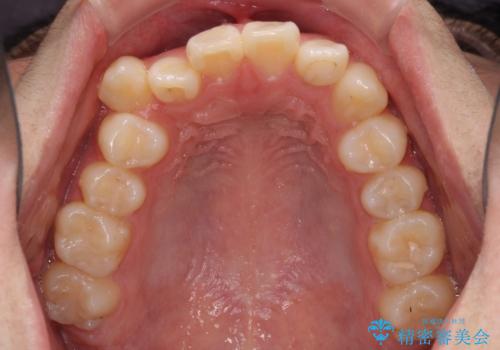

- 八重歯を気にして来院された高校生の患者様です。

ボディーコンタクトの激しい部活動を行っているため、補助装置とインビザラインを用いて、部活動を継続しながら治療を行うこととしました。

八重歯を効率よく改善するため、補助装置を使用して上顎の奥歯を後方に移動させました。

部活動をしながらでしたが、マウスピースをしっかりと装着してくださったので、1年半程度で終了することができました。